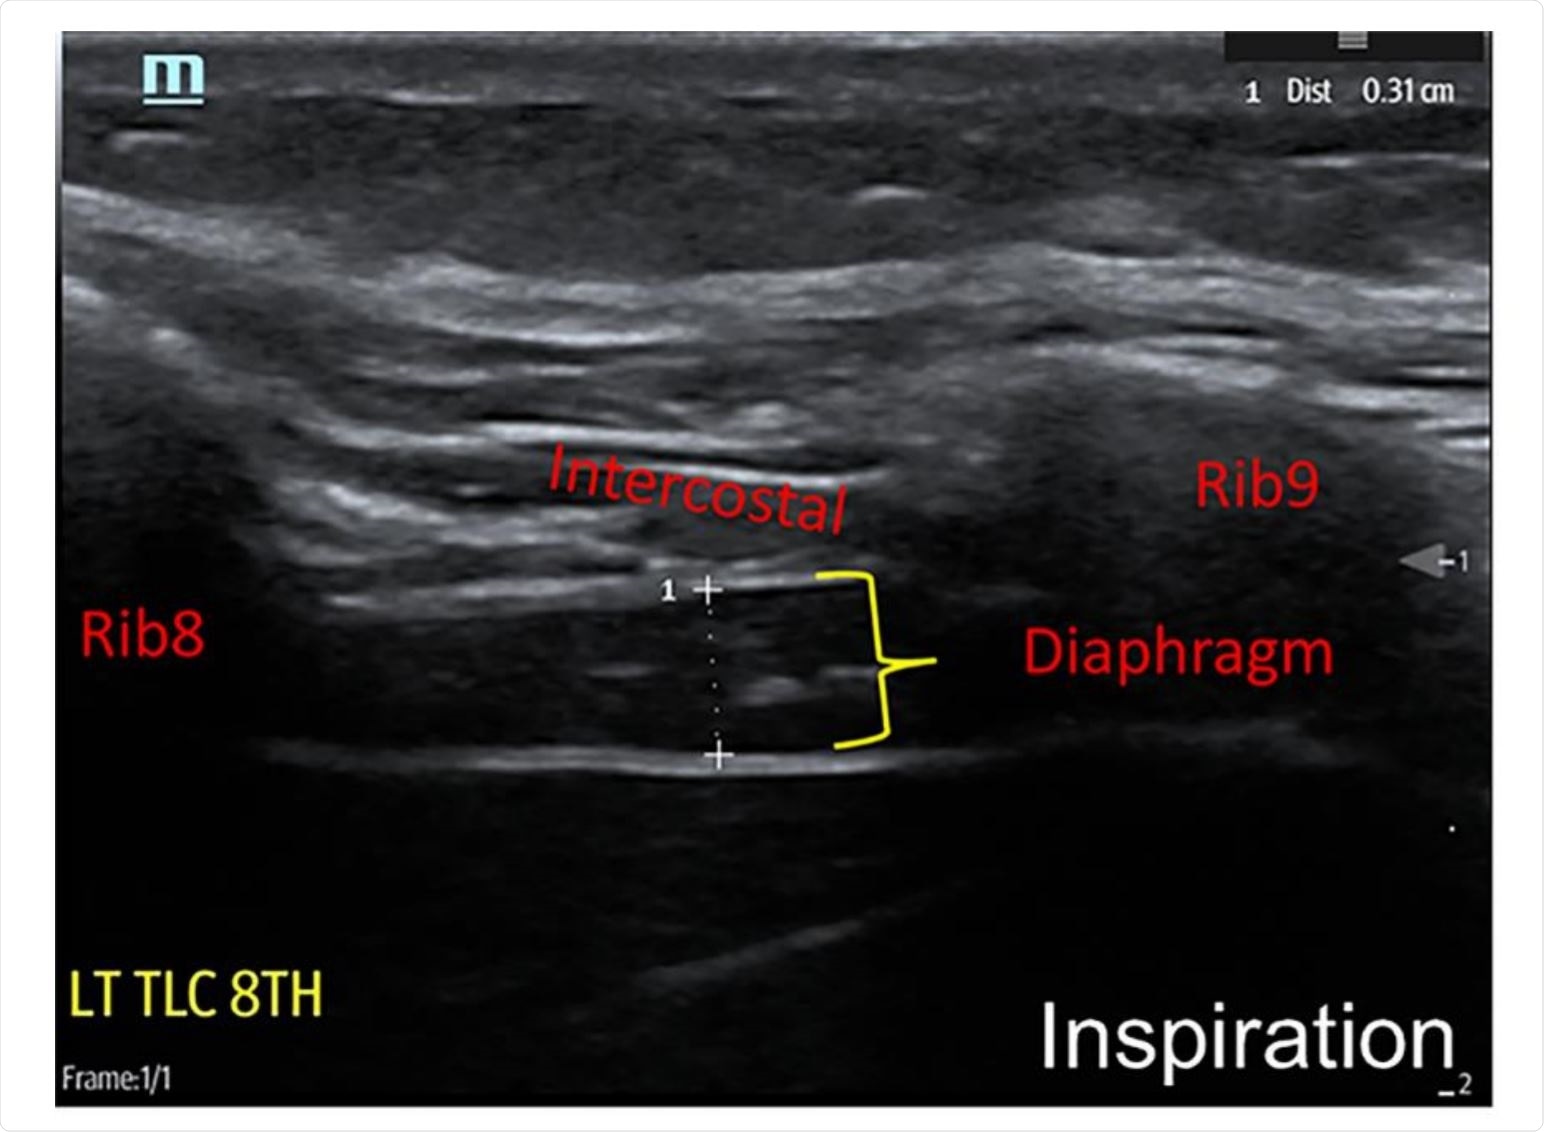

Technique for neuromuscular ultrasound examination of hemi-diaphragm

Technique for neuromuscular ultrasound examination of hemi-diaphragm. Image Credit: medrxiv.org/content/10.1101/2020.12.10.20244509v1.full.pdf

A portable ultrasound system was used to assess the diaphragm muscle; more specifically, individual characteristics were used to guide the selection of either a 6-14 MHz linear array or a 2-5 MHz curvilinear array in order to maximize the image clarity.

In any case, diaphragm thickness was assessed at the maximum inspiration and end of expiration, while the thickening ratio has been calculated as thickness at maximal inspiration divided by thickness at end-expiration.